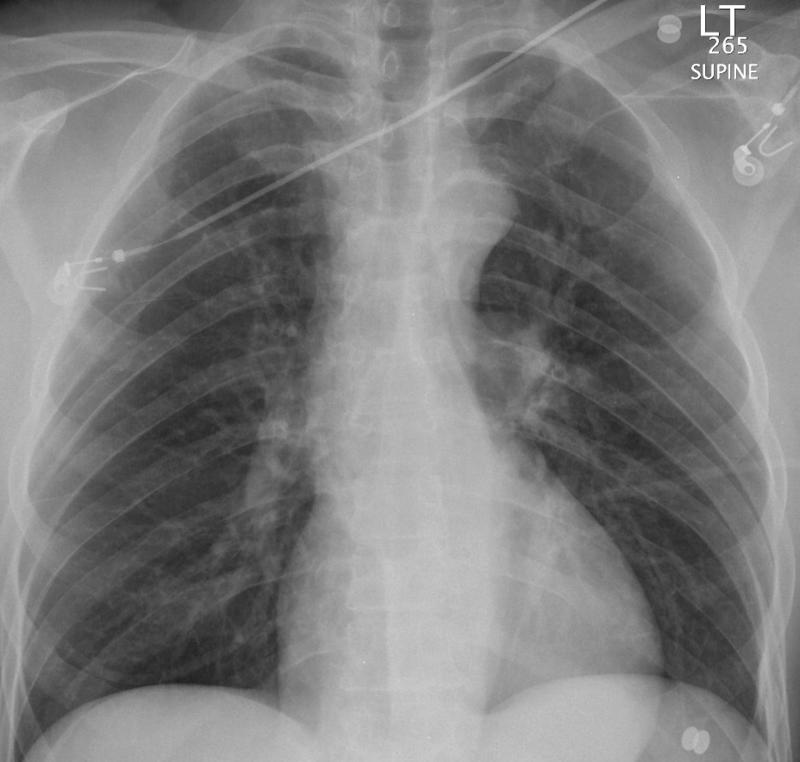

Gallery Blunt Chest Trauma Spine trauma Case 2a

Case 2a